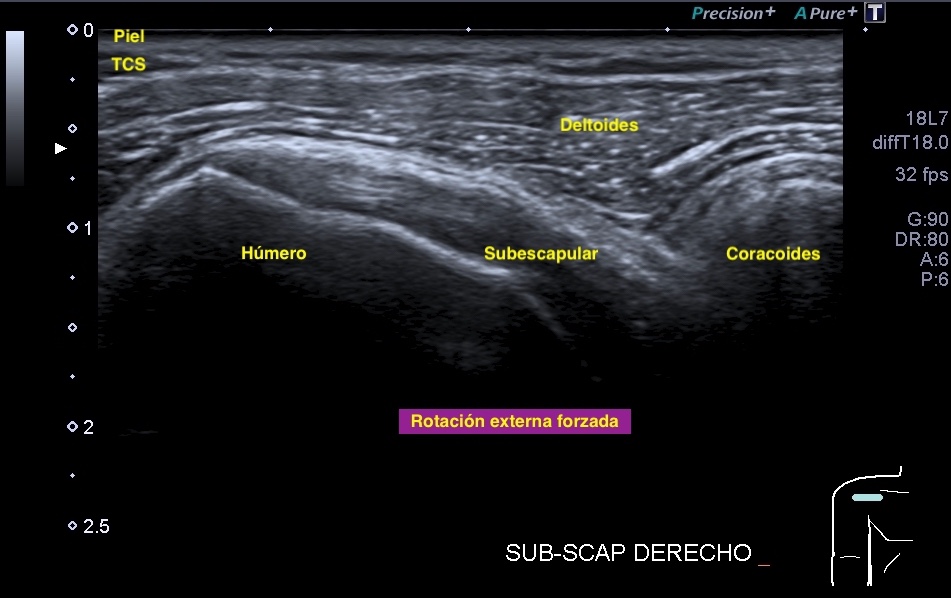

357. Kilopascales (kPc) en Elastrografía. Lo que el TSID debe saber.

Cuando hablamos de medicina moderna, las tecnologías de imagen han revolucionado la forma en que diagnosticamos y tratamos una variedad de enfermedades. Entre estas tecnologías se encuentra la elastografía, un método no invasivo para evaluar la rigidez de los tejidos internos del cuerpo. Pero, ¿alguna vez te has preguntado cómo se mide esta rigidez? Aquí es donde entran en juego los kilopascales (kPa). En este post, exploraremos qué son los kilopascales, su importancia en la elastografía y cómo se utilizan en la práctica médica.

La Importancia de los Kilopascales en Elastografía

La elastografía es una técnica que mide la rigidez o elasticidad de los tejidos blandos, como el hígado, los músculos y otros órganos. Esta técnica es especialmente valiosa para detectar cambios en la rigidez del tejido que podrían indicar condiciones médicas como fibrosis, cirrosis o tumores. En el ámbito de la elastografía, las medidas de rigidez se expresan típicamente en kilopascales.

• Evaluación Musculoesquelética: Utilizado en ortopedia para evaluar la rigidez de músculos y tendones.

En Tejidos Musculares Principales

La rigidez de los músculos puede variar, pero generalmente son más duros (mayor rigidez medida en kPa) cuando están contraídos y más blandos cuando están relajados.